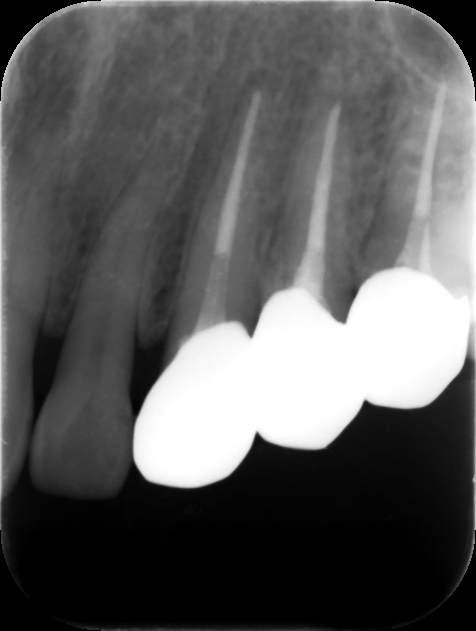

根管充填後レントゲン。歯の痛みや歯茎の腫れが改善したため、バイオセラミックシーラーおよびガッタパーチャにて根管充填を行った。根管治療は2回、2週間で終了。